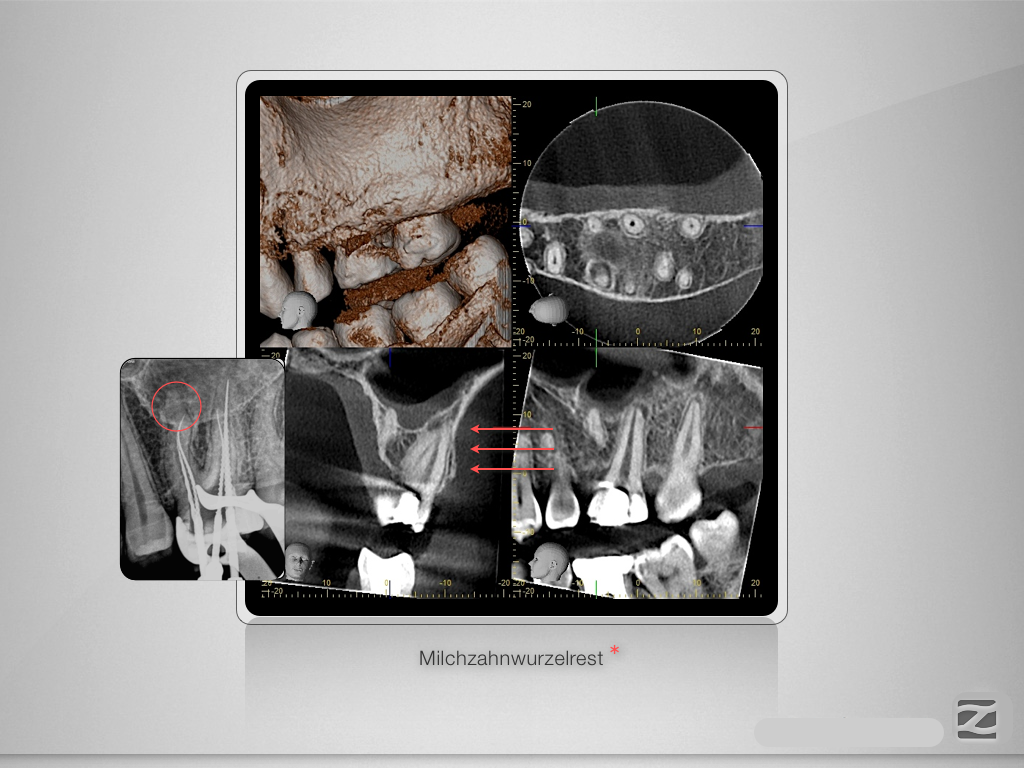

26D.007

Entwarnung